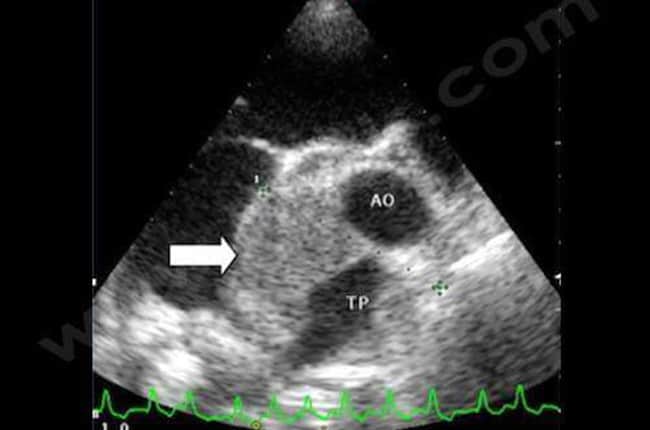

Tumeurs cardiaques chez le chien et le chat